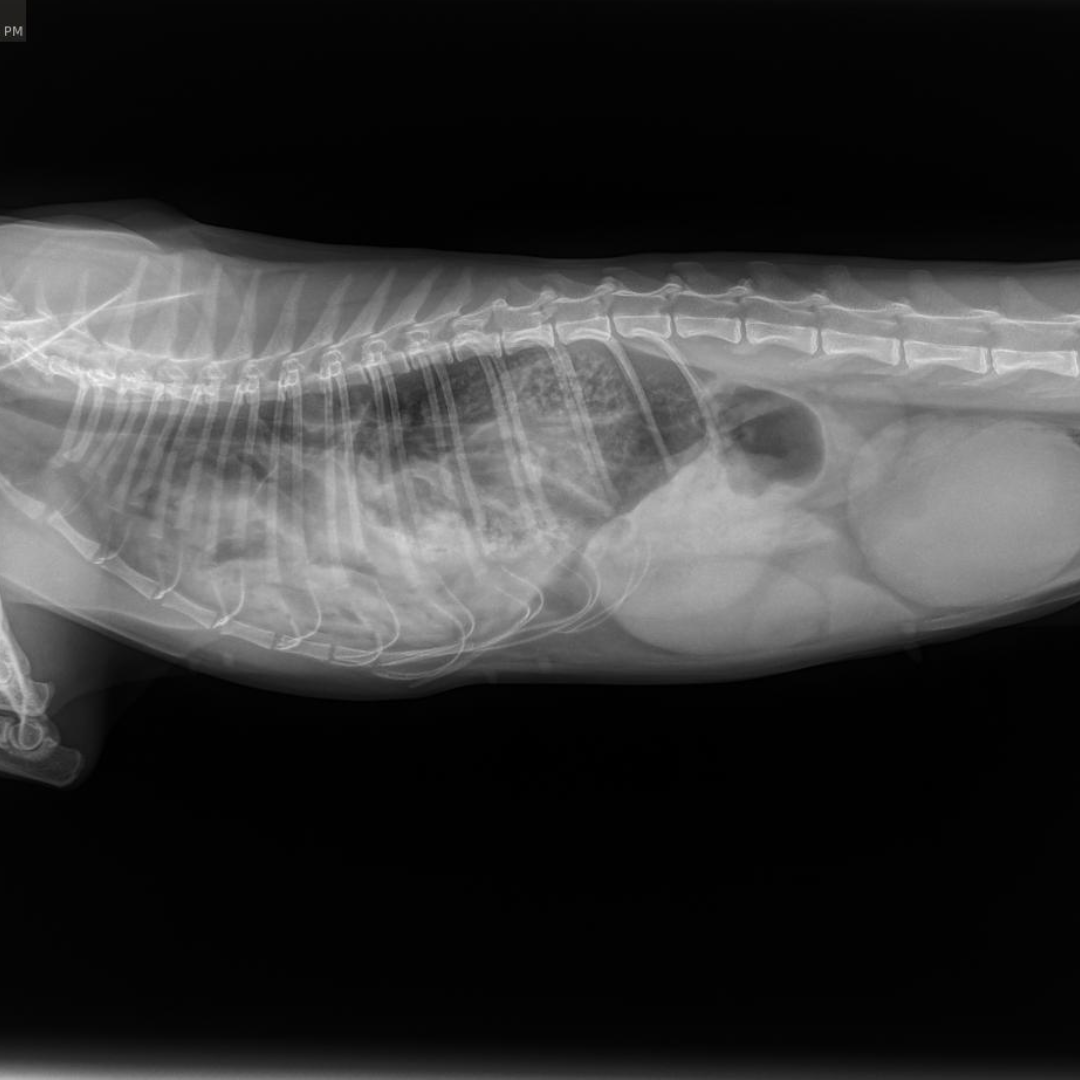

Our veterinary team at the Bredel Clinic acted quickly. Diagnostic X-rays revealed a diaphragmatic hernia, along with concern for a possible internal tumor or an enlarged kidney. A diaphragmatic hernia, as seen in the X-rays below, occurs when a rupture in the diaphragm allows abdominal organs, such as the liver, stomach, or intestines, to move into the chest cavity. This condition is most often caused by severe trauma, like being hit by a car or suffering a major fall, and it can lead to significant respiratory distress, rapid or shallow breathing, muffled heart and lung sounds, and chronic weight loss if left untreated.

During surgery, our veterinarians discovered that Raven’s kidney was severely enlarged, nearly double its normal size, and ultimately had to be removed. Additional scarring was found on her spleen, further confirming that she had likely suffered a significant traumatic injury in her past.